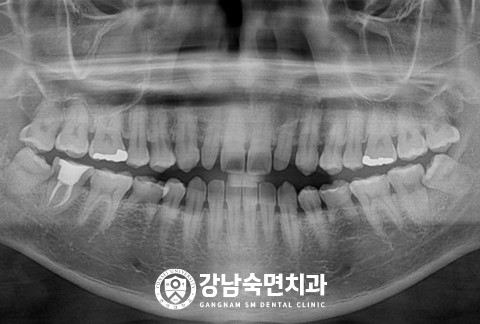

임플란트-전후사진